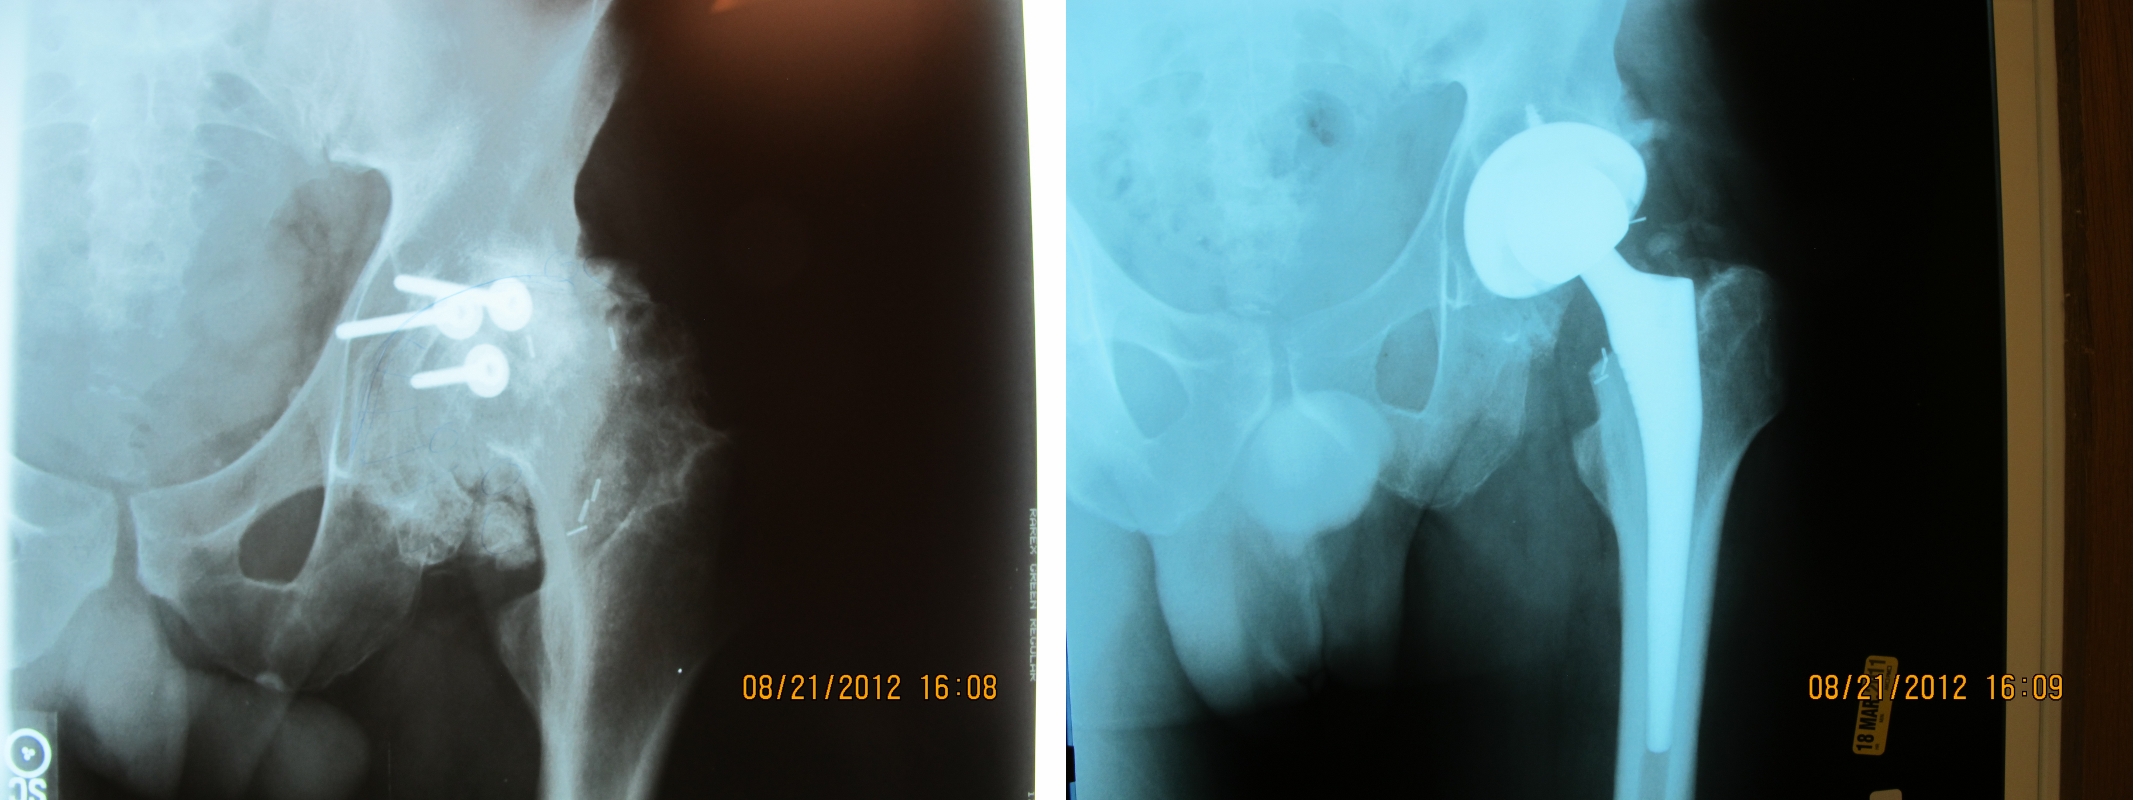

The xrays are from a 40 year old patient who had sustained a posterior acetabular wall fracture. His initial injury had been treated surgically at a major university. Unfortunately, the nature of such injuries is such that most of them develop arthritis despite prompt appropriate care. Two years after his acetabular fracture surgery, his left hip joint is as arthritic as can be. The xray to the right shows the implanted DePuy Corail/Sector hip prosthesis. This solved his pain problem and restored normal gait.